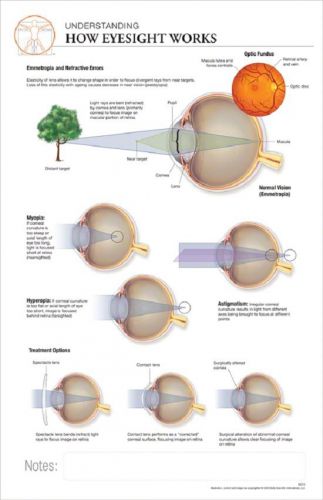

11 x 17 Post-It Anatomical Chart: HOW EYESIGHT WORKS